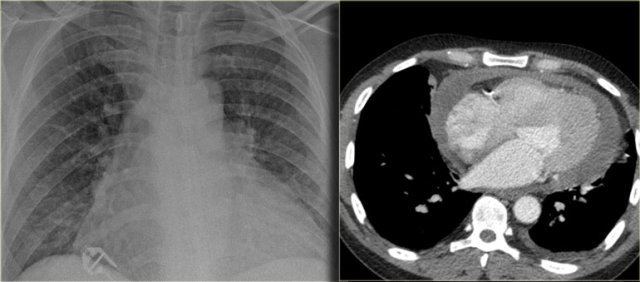

Pericardial effusion

Whenever we encounter a large heart figure, we should always be aware of the possibility of pericardial effusion simulating a large heart.

On the chest x-ray it looks as if this patient has a dilated heart while on the CT it is clear, that it is the pericardial effusion that is responsible for the enlarged heart figure.

Especially in patients who had recent cardiac surgery an enlargement of the heart figure can indicate pericardial bleeding.

This patient had a change in the heart configuration and pericardial bleeding was suspected.

Ultrasound demonstrated only a minimal pericardial effusion.

Continue with the CT.

There is a large pericardial effusion, which is located posteriorly to the left ventricle (blue arrow).

The left ventricle id filled with contrast and is compressed (red arrow).

At surgery a large hematoma in the posterior part of the pericardium was found.

Notice that on the anterior side there is only a minimal collection of pericardial fluid, which explains why the ultrasound examination underestimated the amount of pericardial fluid.

Here another patient who had valve-replacement.

Notice the large heart size.

There is redistribution of the pulmonary vessels which indicates heart failure.

The CT-image shows a large pericardial effusion.

Always compare these post-operative chest films with the pre-operative ones.